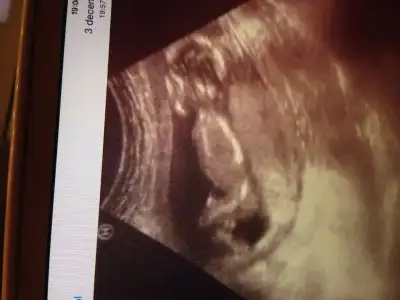

Bizim bebisedee yorum yapar misiniz acaba 15 hafta civari

Merhabalar,daha oncedende koymustum,doktorum bilemedi meraktayim..))) 14+5 gunluk bebisim

Lutfen yorum yaparmisiniz,tesekkurler